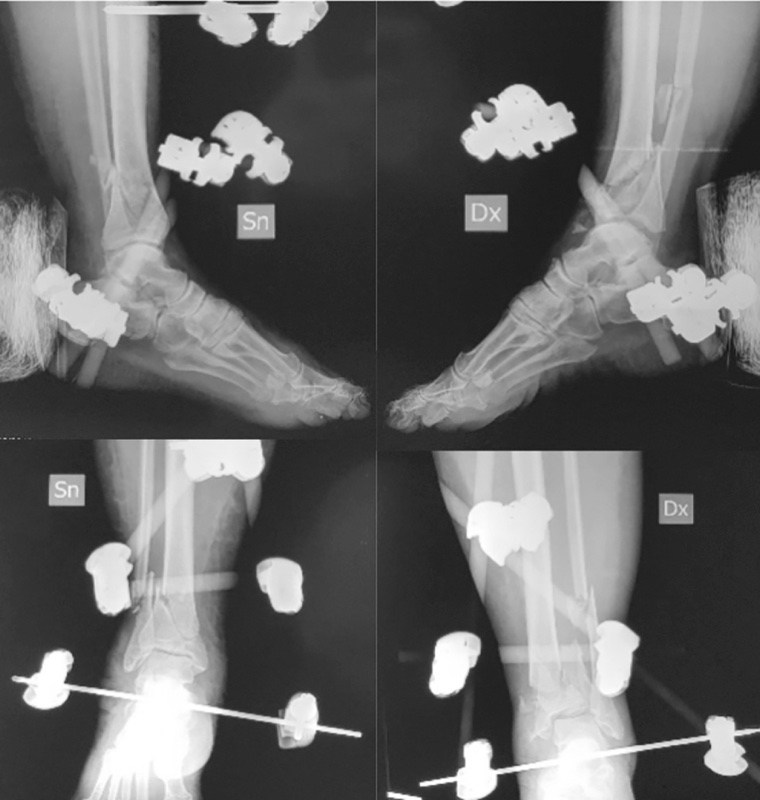

La prima fase consiste ancora nella stabilizzazione temporanea (Fig. 3).

Il protocollo proposto da Sirkin e Sanders prevedeva la sintesi definitiva del perone da effettuare in acuto e la stabilizzazione temporanea con fissatore esterno temporaneo assiale posizionato per via mediale. Nel corso degli anni la fissazione temporanea con fissatore monoassiale è stata via via abbandonata a favore del costrutto a delta che garantiva una stabilità maggiore. Anche la riduzione e sintesi in acuto della frattura di perone è e stata rivisitata nel tempo, la scelta degli autori fu viziata dalla scarsa disponibilità delle vie d’accesso e dalla limitata conoscenza dei pattern di frattura (Fig. 4).